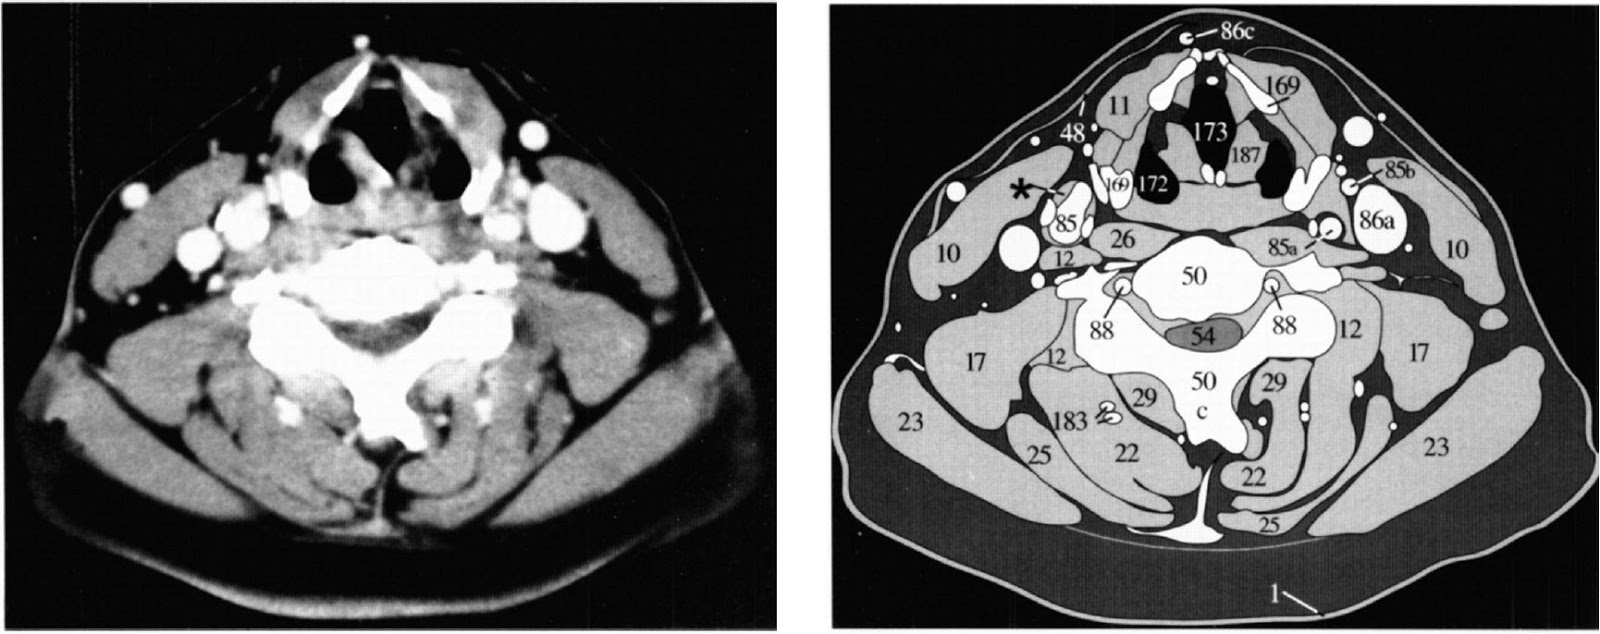

Мскт мягкие ткани

Мскт мягкие ткани 116 фотографий